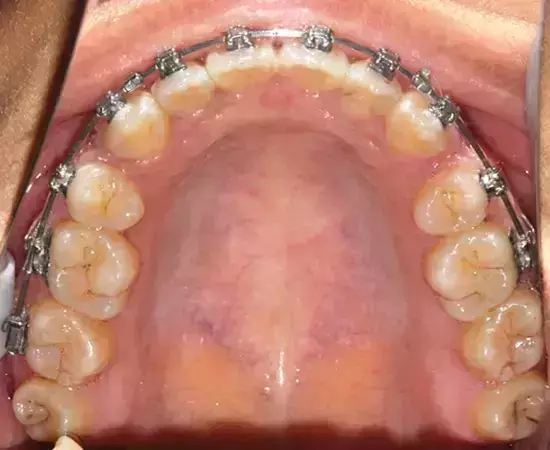

Damon 病例分享:安氏 II 類二分類露齦笑的矯治(董一磊)